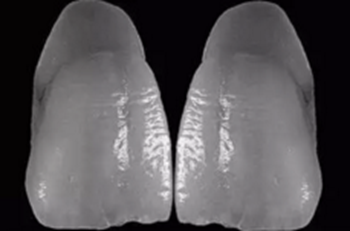

14、在工作模完全就位的義齒

15、在檢測模上可以看出左上1頸線有誤差